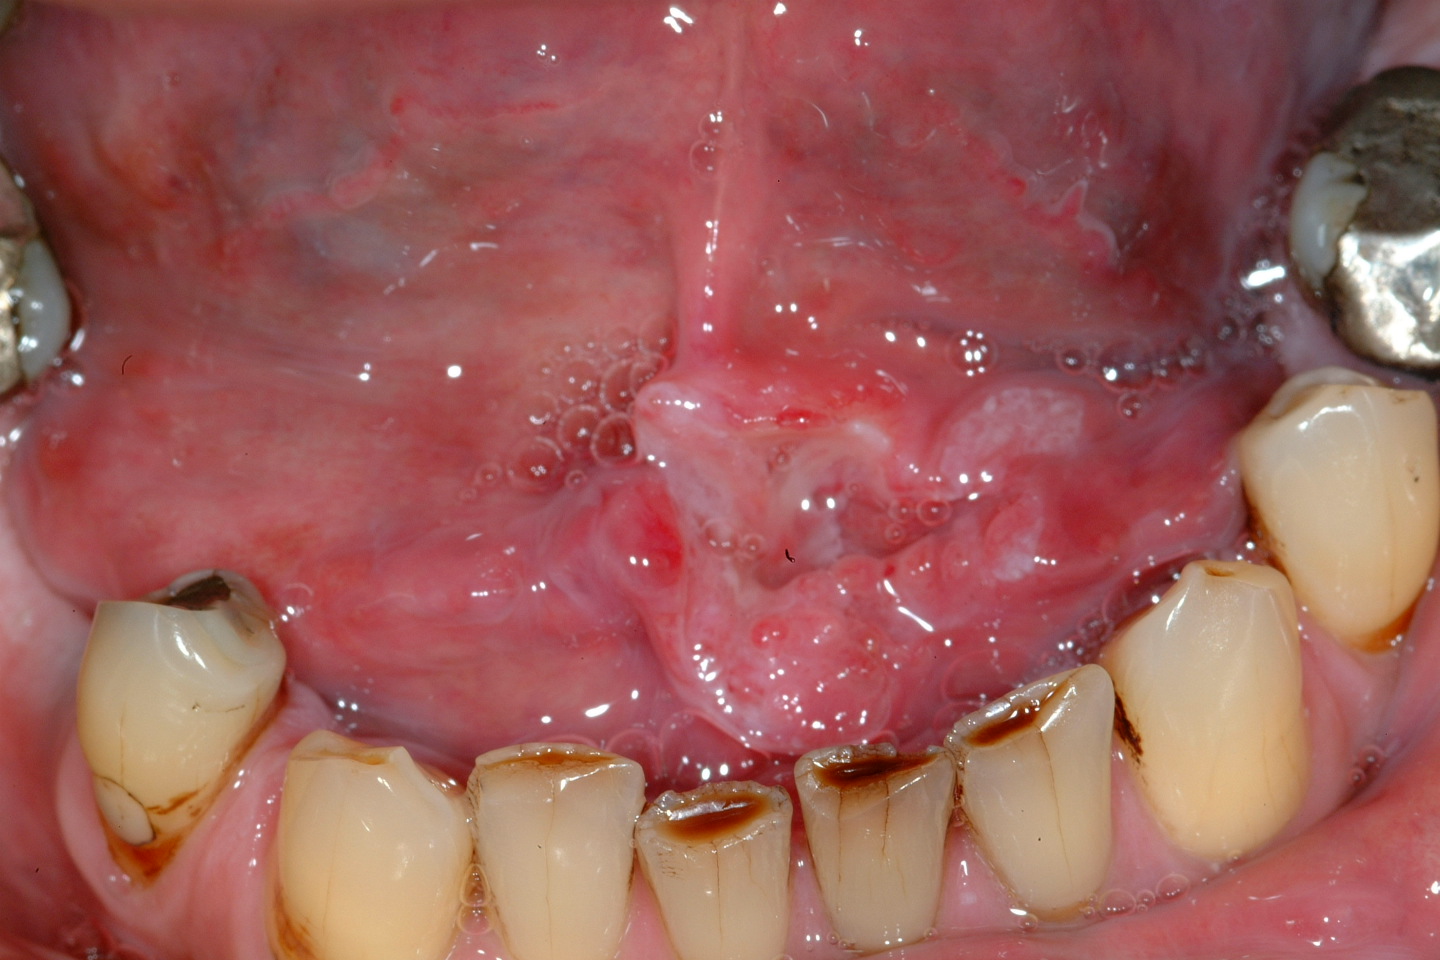

Cancers Of The Floor Of The Mouth

Floor Of The Mouth Cancer

Floor Of The Mouth Cancer Causes Symptoms Treatment Survival

Malignant Tumors Of The Floor Of The Mouth Background

Cancers Of The Floor Of The Mouth

Lesion On The Anterior Floor Of The Mouth With Irregular

Clinical Assessment Of A Squamous Cell Carcinoma Located In

Cancers Of The Floor Of The Mouth

Floor Of The Mouth Cancer Japan Pdf Ppt Case Reports

Squamous Cell Carcinoma Of The Floor Of The Mouth In